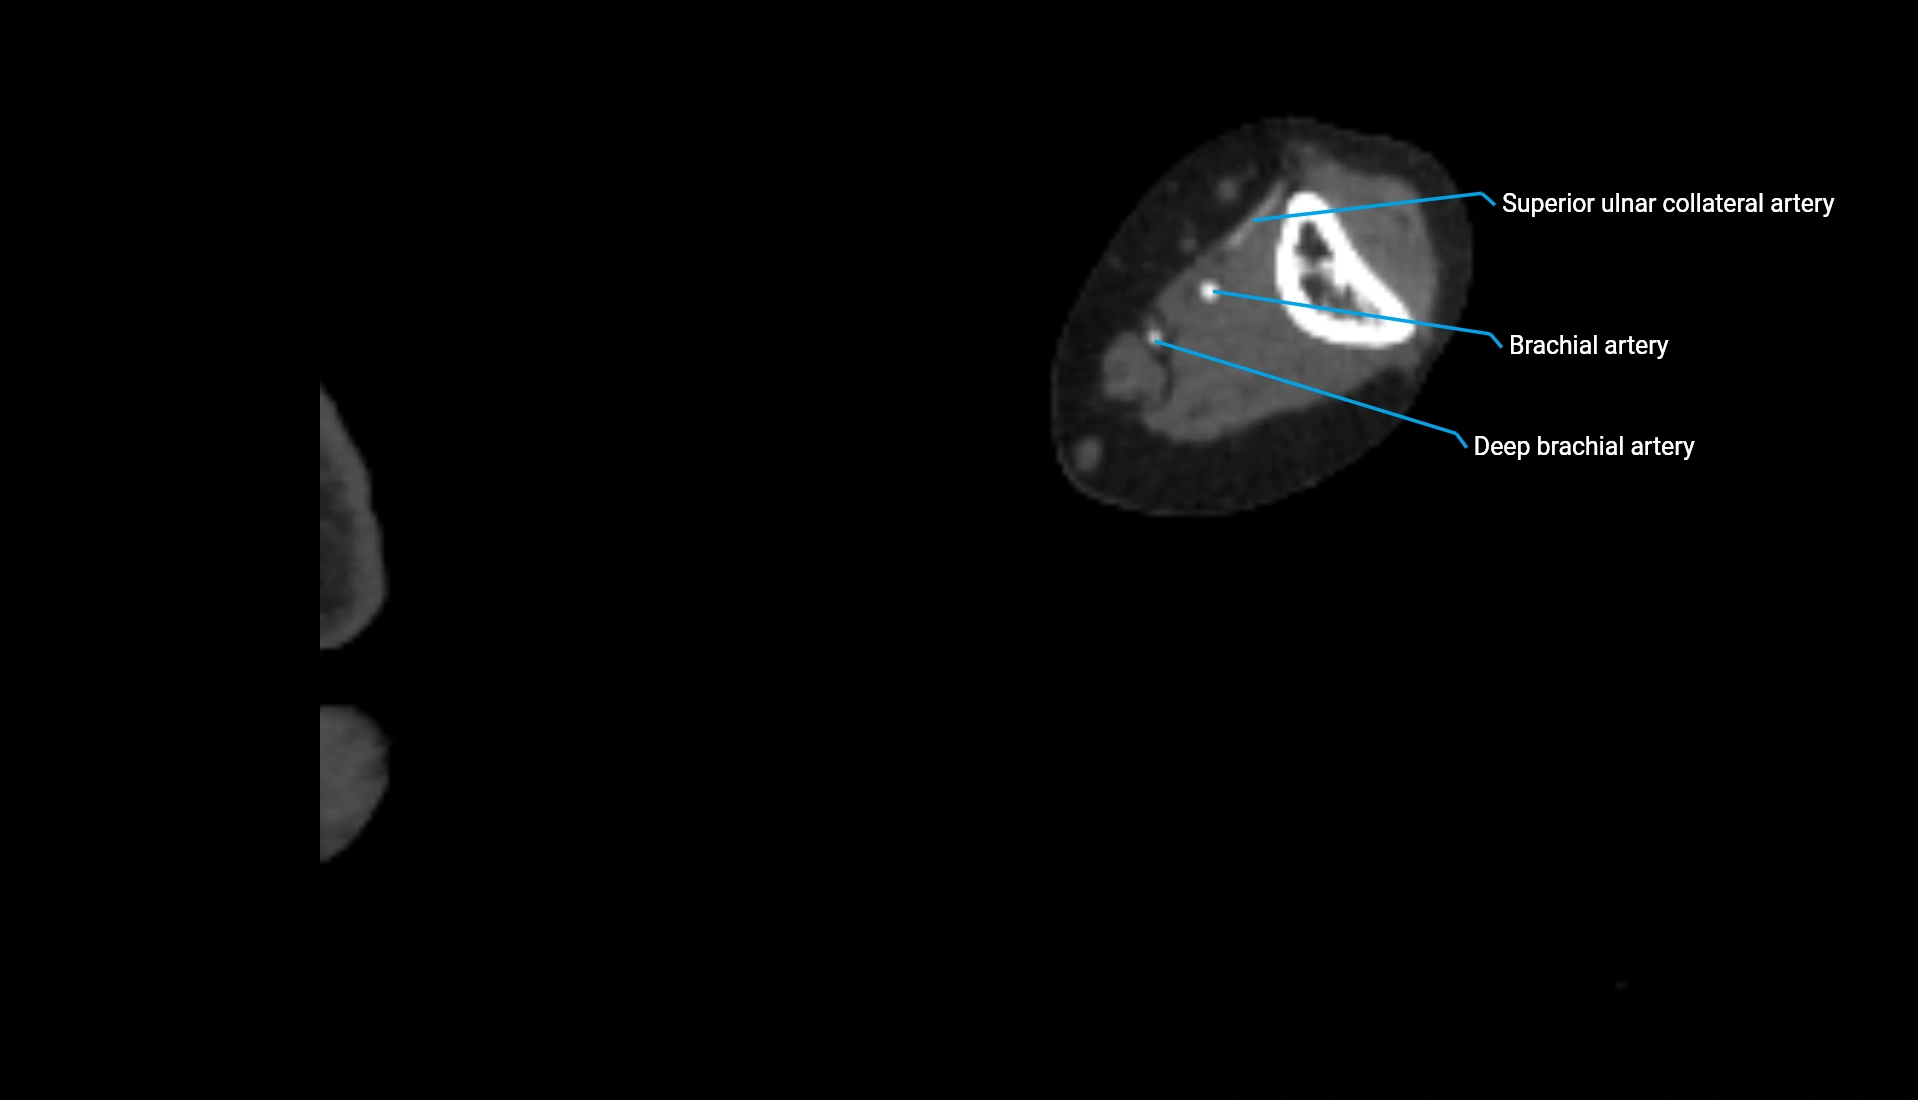

CT Appearance

Non-Contrast CT:

• Cortex: High-density, sharply defined

• Subchondral bone: Dense cancellous matrix

• Articular surface: Smooth concave contour articulating with the capitellum

• Excellent for evaluating bone integrity, alignment, and subtle fractures

Post-Contrast CT:

• Bone: No enhancement

• Joint capsule and synovium: Mild enhancement outlining the joint

• Improves contrast between soft tissues and bony margins

• Useful in detecting subtle joint abnormalities or postoperative changes